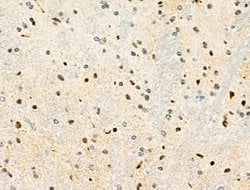

Invitrogen™ Phospho-PDX1 (Ser66) Polyclonal Antibody

Antibody detects endogenous levels of PDX1 only when phosphorylated at Ser66.

| Immunohistochemistry (Paraffin), Western Blot, Immunocytochemistry | |

| Human, Mouse, Rat | |